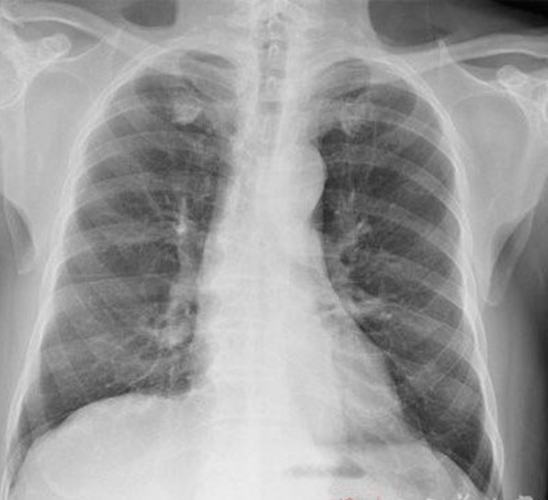

肺腺癌圖片

左肺腺癌術後胸腔內

右上肺腺癌

右下肺腺癌 的